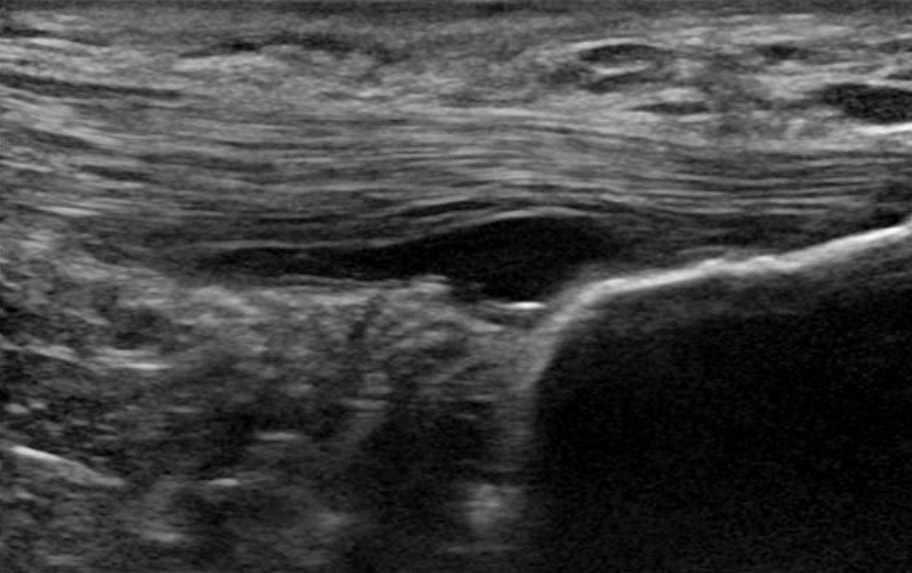

2. We zijn niet in staat om degeneratieve peespathologie te repareren/genezen. Met andere woorden, geen enkele operatie, geen enkele schokgolftherapie, geen enkele injectie en zelfs geen enkele oefening zijn in staat om een gedegenereerde pees te herstellen of te genezen. Docking et al. (2019) redeneren dat met weinig vermogen om trekbelasting te voelen, de cellen in het degeneratieve deel van de pees ondergestimuleerd kunnen zijn en niet de nodige mechanische stimuli ontvangen om te remodelleren, wat de beperkte capaciteit van de pathologische pees om te remodelleren en te normaliseren verklaart. Hoewel u denkt dat dit misschien slecht nieuws is, is het goede nieuws: het is ook niet nodig. Een studie van Tsehaie et al. (2017) toonden aan dat 24 weken excentrische oefeningen voor de achillespees geen veranderingen buiten de grenzen van de detecteerbare verandering in de pees teweegbrachten, maar toch verbeterden patiënten. Zij vonden ook dat o MRI-parameter op baseline de verandering in symptomen voorspelde, dus zelfs als je MRI er verschrikkelijk uitziet, doet het er niet toe.

6. Een pathologische pees heeft meer goede structuur dan een normale pees(Docking et al. 2015). Dit betekent dat we deze pezen kunnen belasten omdat we veel goed weefsel hebben. Therapieën voor peespathologie zijn niet nodig, omdat we de structuur van het pathologische deel toch niet kunnen veranderen. Daarom kwamen Docking en collega's met de uitspraak "Behandel de donut, niet het gat" - met andere woorden, concentreer je op de gezonde structuur en niet op het pathologische deel.

Een pathologische pees heeft meer goede structuur dan een normale pees (Docking et al. 2015)